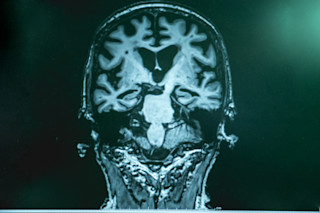

At the hospital, Auguste was under the care of Alois Alzheimer, a doctor who diagnosed her with “presenile dementia.” When she died in 1906, Alzheimer conducted an examination of her brain. He found the cerebral cortex had thinned. He also observed “senile plagues” and neurofibrillary tangles.

Scientists are still trying to understand both the genetic and environmental influence on both early-onset and late-onset Alzheimer’s disease. Problematically, scientists know that people who develop Alzheimer’s disease begin experiencing neurological changes decades before they show symptoms.

For people with late-onset Alzheimer’s disease who are diagnosed in their 70s, Beecham says the changes in their brain likely began in their 50s. For those with early-onset, the change likely starts five to 10 years before symptoms present.